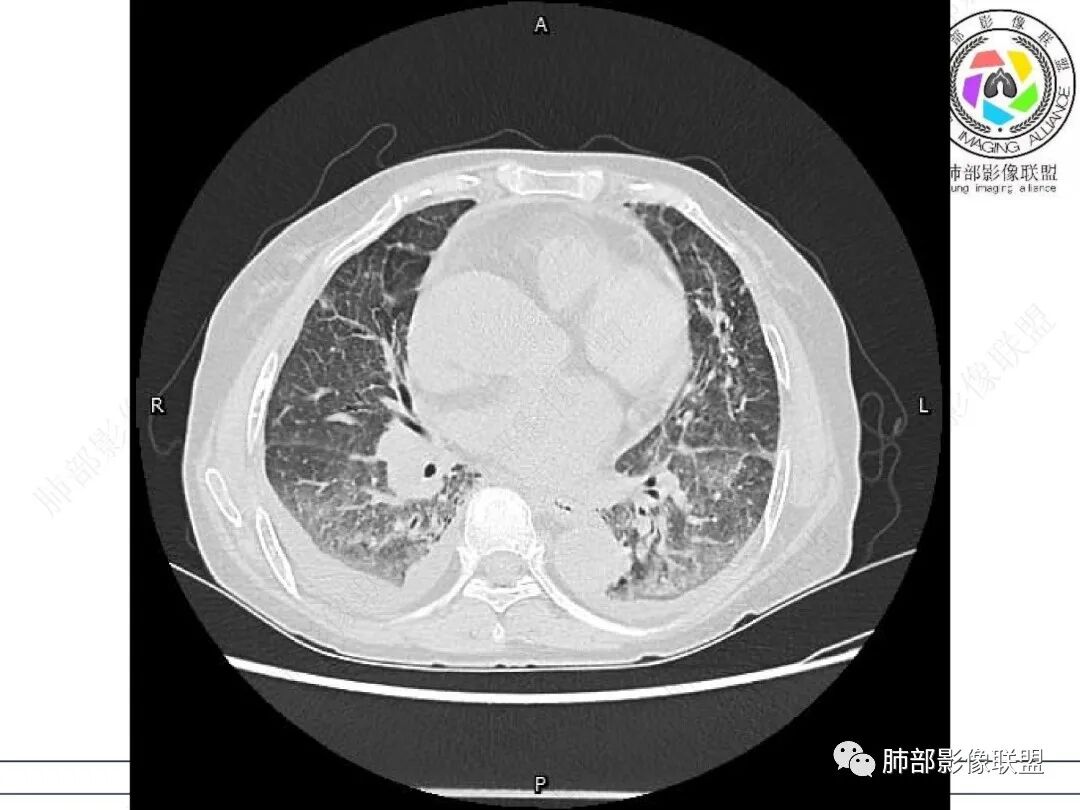

两肺叶后肋膈角区见多发蜂窝状结构破坏表现,双肺叶小叶间隔增厚,左肺上叶后段及舌段和右肺中叶胸膜炎性肉芽肿特点,双侧胸腔少量积液,有类风湿性关节炎治疗史,结缔组织相关性间质性肺病。

发热,有类风湿性关节炎、糖尿病基础病,长期口服激素及免疫抑制剂,双肺多发磨玻璃影及小叶间隔增厚,蜂窝影,支气管扩张考虑非特异性间质性肺炎存在,左肺上叶不规则结节影,周围长毛刺局部肺气肿,考虑慢性炎症,结合pct及crp升高考虑细菌感染,另真菌g升高考虑结合宿主因素,真菌感染需要积极排除。

老年,外阴溃疡加发热,感染指标明显有异常,血气分析,过度呼吸及低氧血症,宿主因素,糖尿病和激素,基础疾病RA。影像,双下肺体积有缩小,有蜂窝?双肺磨玻璃,多发结节,双侧胸水。树芽不明确。是否有旧片,这个患者有UIP背景,是否感染或者UIP急性加重,或者基础上合并肺栓塞及肺水肿?长期激素,没有提供CD4细胞亚群,存在2种情况,1,风湿病没有压制住,肺考虑CTD相关性间质改变,压制过猛,结合感染指标,奴卡是有可能的。激素加糖尿病,结核也带排,激素加磨玻璃加G实验阳性,PCP也带排,临床信息太少,进一步排查

老年女性,类风湿关节炎病史多年。发热。以两肺下叶为主弥漫磨玻璃及网格状透亮影,透亮度减低,局部小蜂窝状改变;两肺胸膜下散在几枚实性病灶;双侧胸腔积液。考虑RA-ILDNSIP

双下肺后肋膈角区见多发蜂窝,小叶间隔增厚,磨玻璃改变,,双侧胸腔少量积液,Crp明显升高,有类风湿性关节炎,糖尿病。甲氨蝶呤,托法替布治疗。会阴溃疡。考虑:1.免疫妥协2.pcp?巨细胞病毒?3.甲氨蝶呤致肺损伤?4.Ctd-ild.

两下肺多发蜂窝状表现,双肺小叶间隔增厚,双肺磨玻璃影及部分炎性肉芽肿表现,双侧胸腔积液,有类风湿性关节炎治疗史,结缔组织相关性间质性肺病。患者C反应蛋白和降钙素原都高,是否合并细菌感染

女,71,外阴疼痛2周,发热1周。类风关、高血压、高血糖、卵巢囊肿、肠粘连、胆囊结石等病史及相关药物治疗史。胸部CT:两肺弥漫磨玻璃,血管束增粗,两下肺后肋膈角多发蜂窝,对称分布,双侧胸腔少量积液,纵隔窗心脏大血管影明显增宽。考虑混合性病变,CTD-ILD,并肺水肿?并PJP?。

双肺下叶多发蜂窝影,双肺小叶间隔增厚,双肺磨玻璃影,双侧胸腔积液,有类风湿性关节炎,考虑结缔组织相关性间质性肺病,合并感染

①影像表现复杂:较弥漫间质性改变,对称磨玻璃密度为主,小叶间隔增厚,有一定重力分布趋势,未见明显纤维化,气囊及蜂窝位于肺边缘,未见典型“月弓征”。心脏影增大,双侧胸腔积液。

这即可见于间质性肺病,也可见于真菌感染(如PJP)、病毒感染,类风湿,以及肺水肿等等。

一般而言,如存在磨玻璃密度影浑浊,有重力分布趋势,肺表面蜂窝影,胸腔积液等等,并不常见于单纯PJP,除非其他因素叠加。

患者存在肺水肿应当是合理的解释。其他旁证还有,心脏影增大,肾小球滤过率降低,双侧胸腔积液等等……